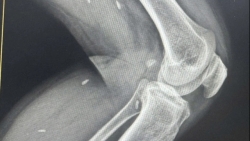

Phát hiện nhiều kén sán trong chân bệnh nhân

Trung tâm Y tế khu vực Thạch Hãn, tỉnh Quảng Trị cho biết, vừa ghi nhận trường hợp bệnh nhân với nhiều kén sán ở chân.